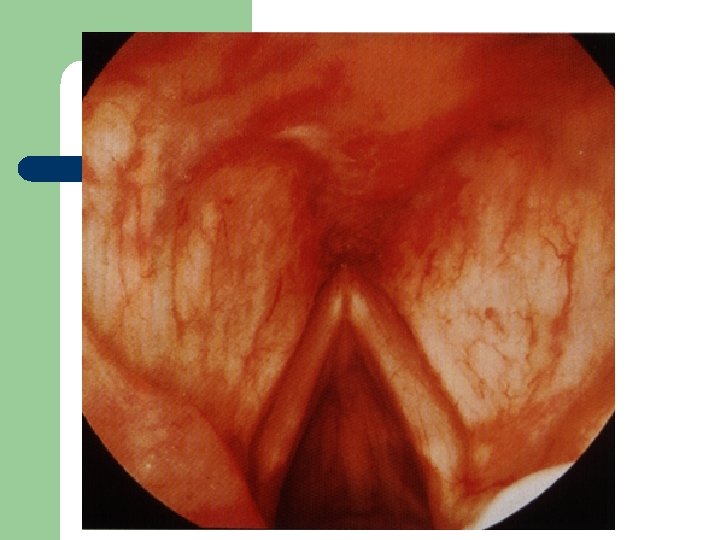

Vývoj dětské chraptivosti l 1. 2. 3. 4. Průvodním jevem při dětské chraptivosti je pokašlávání a pochrchlávání. Nález na hlasivkách postupuje takto: Hyperemické (překrvené hlasivky, Hypertrofické, vřetenovité zduření, hlasivkový uzávěr je neúplný a hlas má dyšnou příměs, ventrikulární řasy se začínají vyklenovat Zpěvácké uzlíčky, nejčastěji na hranicích přední a střední třetiny hlasivek Atrofie hlasivek až s podélnou rýhou, při fonaci nedomykavost uzávěru.